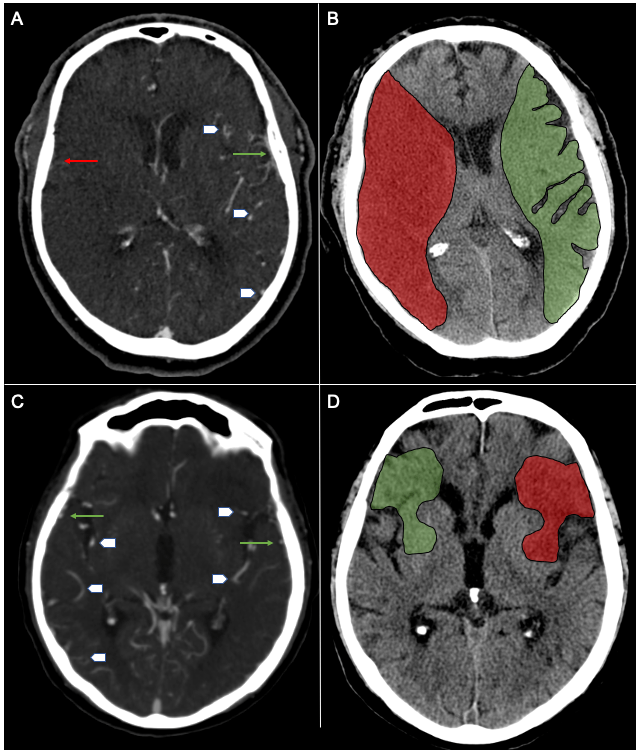

Automated Cerebral Hemorrhage Detection Using RAPID

Heit JJ, et al. (2021) AJNR Jan;42(2):273-278. doi: 10.3174/ajnr.A6926. Epub 2020 Dec 24.